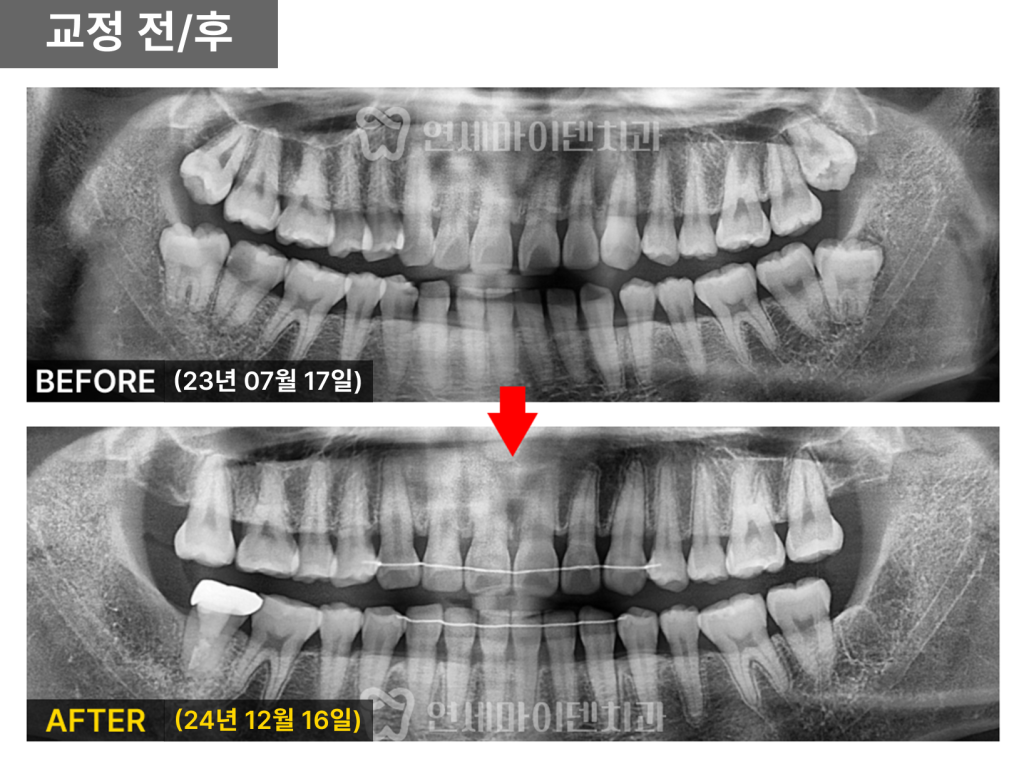

치아교정 전후 비교

치아 배열이 전체적으로 더욱 정돈되었으며,

가장 눈에 띄던 위 앞니 사이 공간이

완전히 닫힌 모습을 확인할 수 있었습니다.

파노라마 사진에서도 사랑니는 모두 발치되었고,

충치 치료와 크라운 보철까지 완료되어

전체적인 구강 상태가 개선되었습니다.

치근 평행도 또한 양호하며,

치근 흡수 없이 건강한 치조골 유지 상태를 보였습니다.